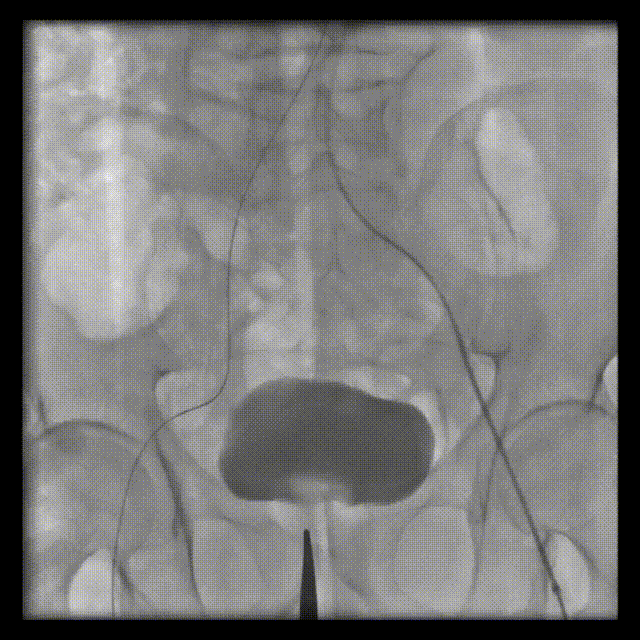

術(shù)前CT